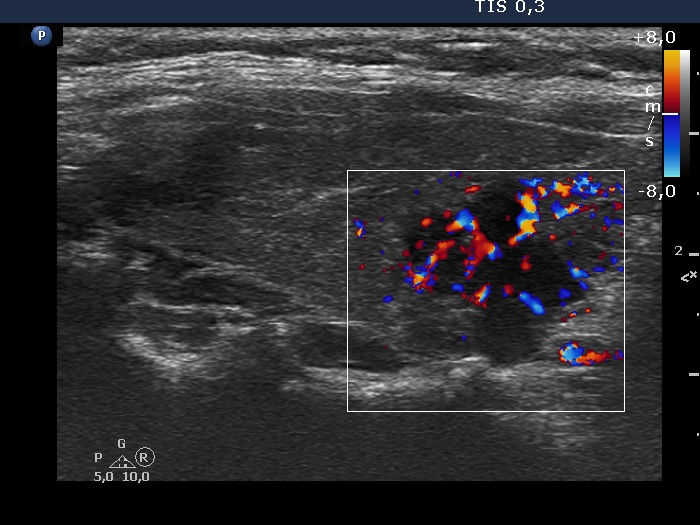

Right lobe, longitudinal scan

Right lobe, longitudinal view, color Doppler mode. The cluster of lesion presents a significantly increased vascularization.